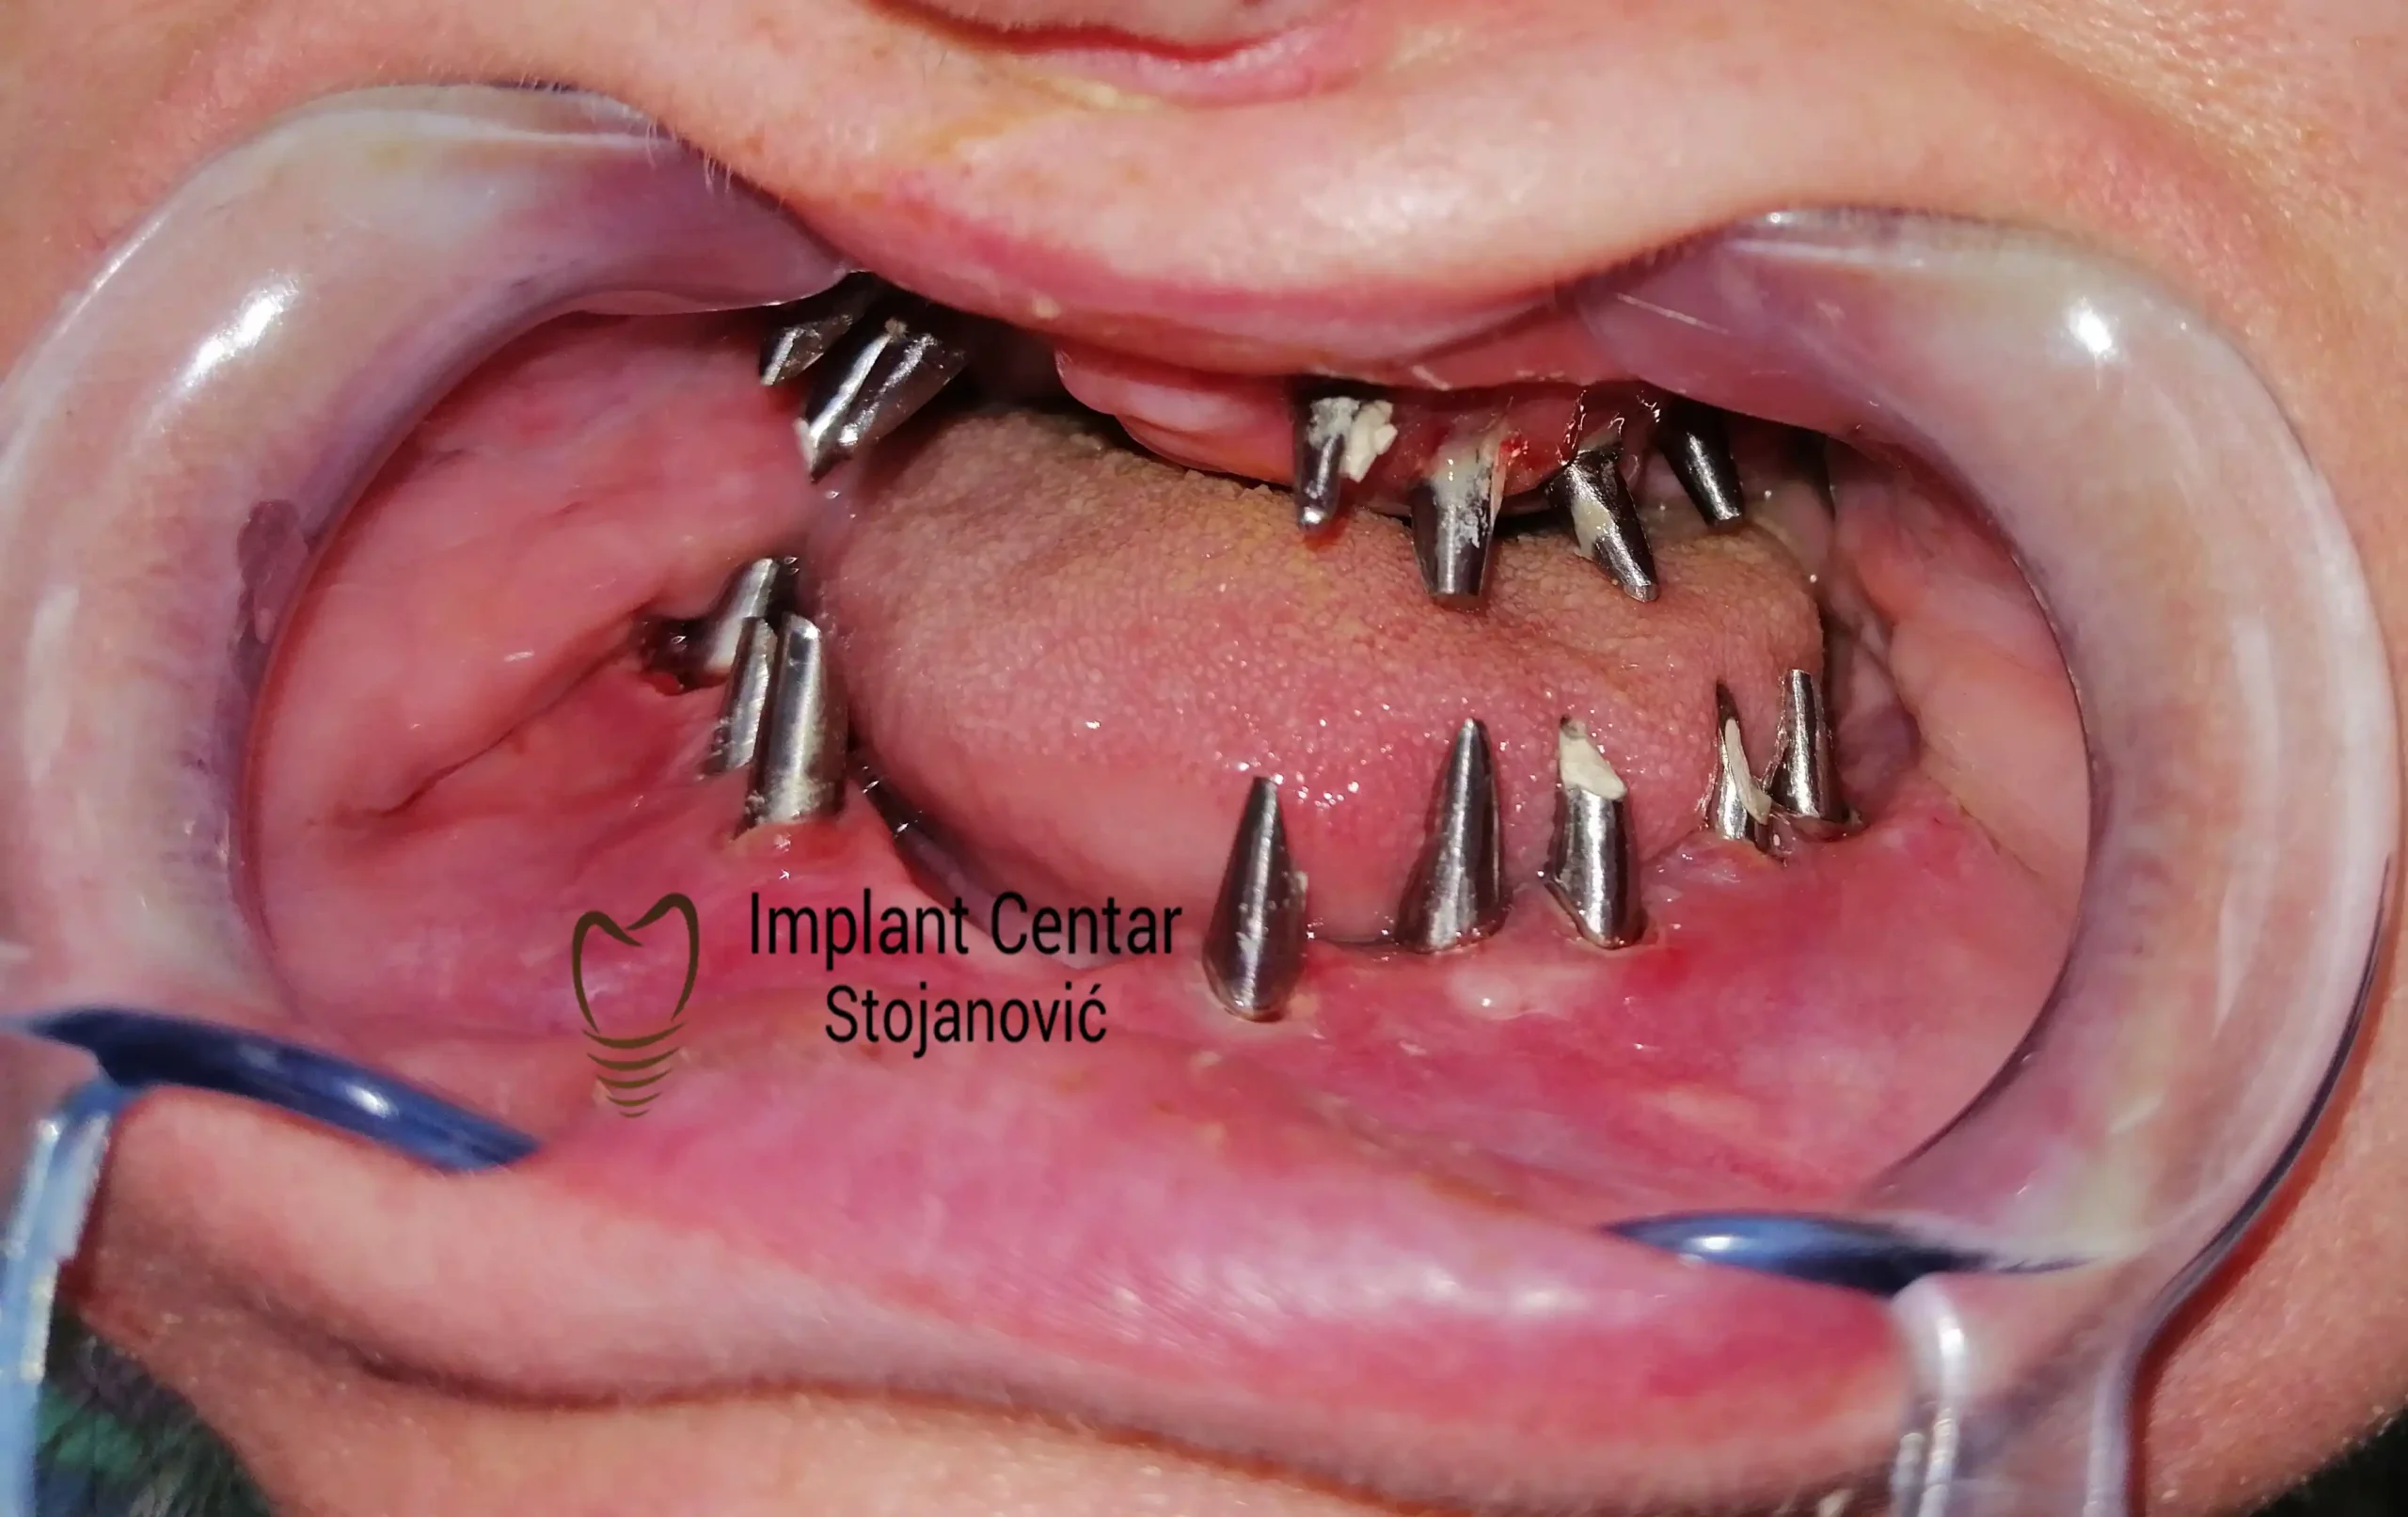

Na slici 1. i slici 2. prikazan je izgled pacijenta pre početka terapije – klinički i rendgenološki.

Nakon vađenja zuba, ugrađeni su implantati. Na slici 3 prikazan je ortopan snimak sa ugrđenim implantatima. Tokom perioda osteointegracije, pacijent je bio zbrinut fiksnim privremenim krunicama na implantatima, koje su izrađene samo dva dana nakon hirurške intervencije.